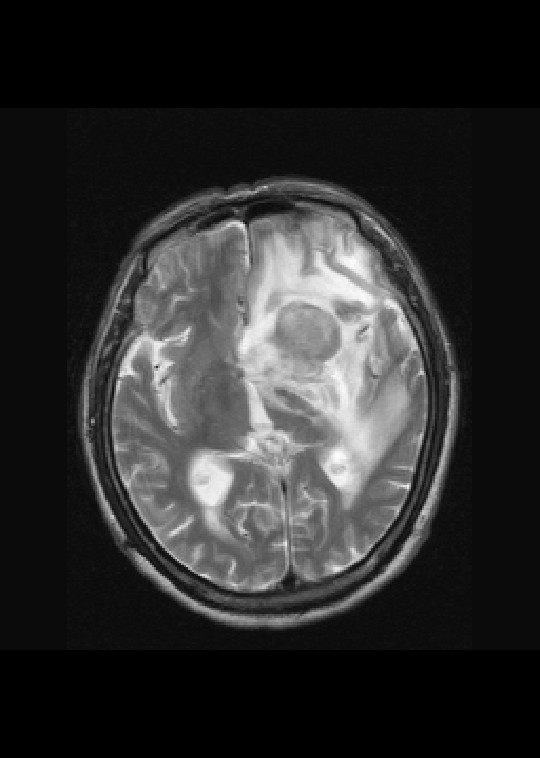

左侧基底节区病灶t1wi呈不均匀稍低信号,t2wi呈稍高信号,周围伴有水肿。增强扫描呈均匀团块样或者抱拳样明显强化,相邻的柔脑膜亦见线样强化。首先考虑淋巴瘤。可惜没有ct平扫,如果ct平扫病灶呈高密度,那么更支持pcnsl的诊断。

左侧基底节区病灶t1wi呈不均匀稍低信号,t2wi呈稍高信号,周围伴有水肿。增强扫描呈均匀团块样或者抱拳样明显强化,首先考虑淋巴瘤。